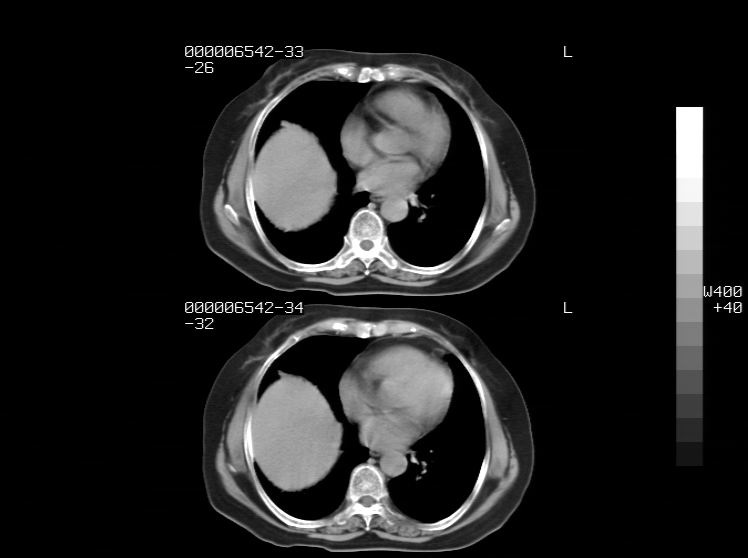

右侧膈膨升,胆囊壁厚,右侧肾脏缺如。病史?

右侧膈膨升,右肾脏切除术后

右侧膈膨升,肝内钙化灶,胆囊壁厚,右侧肾脏缺如。病史?

右膈膨出,肝脏变异,肝内钙化,右肾缺如,脾大。

右侧膈膨升,肝内胆管结石?

右侧肾脏缺如。病史?

右侧膈膨升,胆囊壁厚,右侧肾脏缺如,增强,腔静脉旁是否是移位肾

肝脏变异致膈升高,肝左叶肝内胆管结石.右肾萎缩,左肾代偿肥大.

胆囊ct未见确切异常,请结合b超。右侧肾窝未见确切肾脏影,右肾萎缩?异位?

右侧膈膨升,肝内钙化灶,胆囊壁厚,右肾萎缩或发育不良。